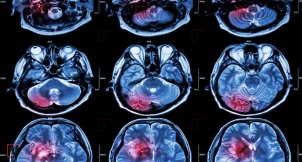

Beyin şişlərində bakteriyalar tapıldı

İsrailin Weizmann Elm İnstitutu tərəfindən aparılan araşdırma, beyin şişlərində müxtəlif bakteriyaların olduğunu üzə çıxardı. Bu bakteriyalar, şişlərin müalicəsinə təsir edə bilər və xəstələrin həyat müddətini dəyişdirə bilər. Araşdırma nəticələri Böyük Britaniyanın "Nature Cancer" jurnalında yayımlanıb.

Araşdırma qrupu yüzlərlə beyin şiş nümunəsini analiz edərək, beynin uzun müddət "steril mühit" kimi qəbul edildiyi fikrini rədd etdi. Şişlərdə müxtəlif bakteriyaların "məskunlaşdığı" və bu bakteriyaların miqdarı ilə xəstələrin həyat müddəti arasında əlaqə olduğu aşkarlandı. Məsələn, beyin metastazlarında bakteriyaların sayı və növləri ilkin şişlərə nisbətən daha çoxdur. Xəstəlikdən bir il ərzində dünyasını dəyişən xəstələrin şişlərindəki bakteriya müxtəlifliyi, daha uzun yaşayan xəstələrdən nəzərəçarpacaq dərəcədə yüksəkdir.

Araşdırmada 322 glioblastoma və beyin metastaz nümunəsi analiz edilib. Məlum olub ki, bakteriyalar həm xərçəng hüceyrələrinin daxilində, həm də ətrafdakı immun hüceyrələrdə mövcuddur. Müxtəlif şiş növləri fərqli bakteriya qruplarını daşıyır. Maraqlıdır ki, bəzi bakteriyalar ilkin şişdən metastaz yolu ilə beyinə keçə bilir.

Araşdırma, bakteriyaların beyin şişlərində yerləşməsinin beyinin bölgələrinə görə dəyişdiyini göstərdi. Beyinin arxa hissəsindəki şişlərdə bakteriyalar daha çox və müxtəlifdir, ön hissədəki şişlərdə isə bu göstəricilər daha aşağıdır. Alimlər bu fərqin beyinin müxtəlif bölgələrindəki qan dövranı və metabolik mühitlə əlaqəli ola biləcəyini düşünür.